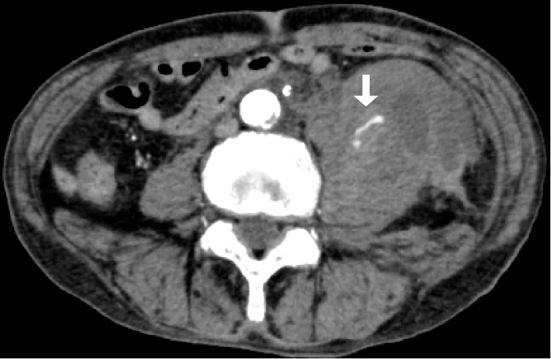

A 73-year-old man receiving hemodialysis and antiplatelets was admitted with a mild case of COVID-19. Heparin was added, and iliopsoas hemorrhage developed. He was successfully treated by interventional radiology. A 76-year-old man receiving hemodialysis and antiplatelets was admitted with mild COVID-19. Heparin was added, and iliacus hemorrhage developed. Despite heparin discontinuation, he died of worsening pneumonia. A 74-year-old man undergoing hemodialysis was admitted with severe COVID-19. Gastrointestinal bleeding developed during continuous hemodiafiltration with heparin. Upon switching to nafamostat and increasing the dose, iliopsoas hemorrhage developed. Despite interventional radiology, he died of infectious complications. Attention to hemorrhagic complications is therefore needed in patients with COVID-19.

一位 73 岁男性,正在接受血液透析和抗血小板治疗,因 COVID-19 轻度感染入院。给予肝素后,发生了髂腰肌血肿。通过介入放射学成功治疗。一位 76 岁男性,正在接受血液透析和抗血小板治疗,因 COVID-19 轻度感染入院。给予肝素后,发生了髂肌血肿。尽管停用了肝素,但他仍因肺炎恶化而死亡。一位 74 岁男性,正在接受血液透析,因 COVID-19 重度感染入院。在使用肝素进行连续性血液透析滤过过程中出现胃肠道出血。改为使用那屈肝素并增加剂量后,发生了髂腰肌血肿。尽管进行了介入放射学治疗,但他还是死于感染性并发症。因此,COVID-19 患者需要注意出血并发症。